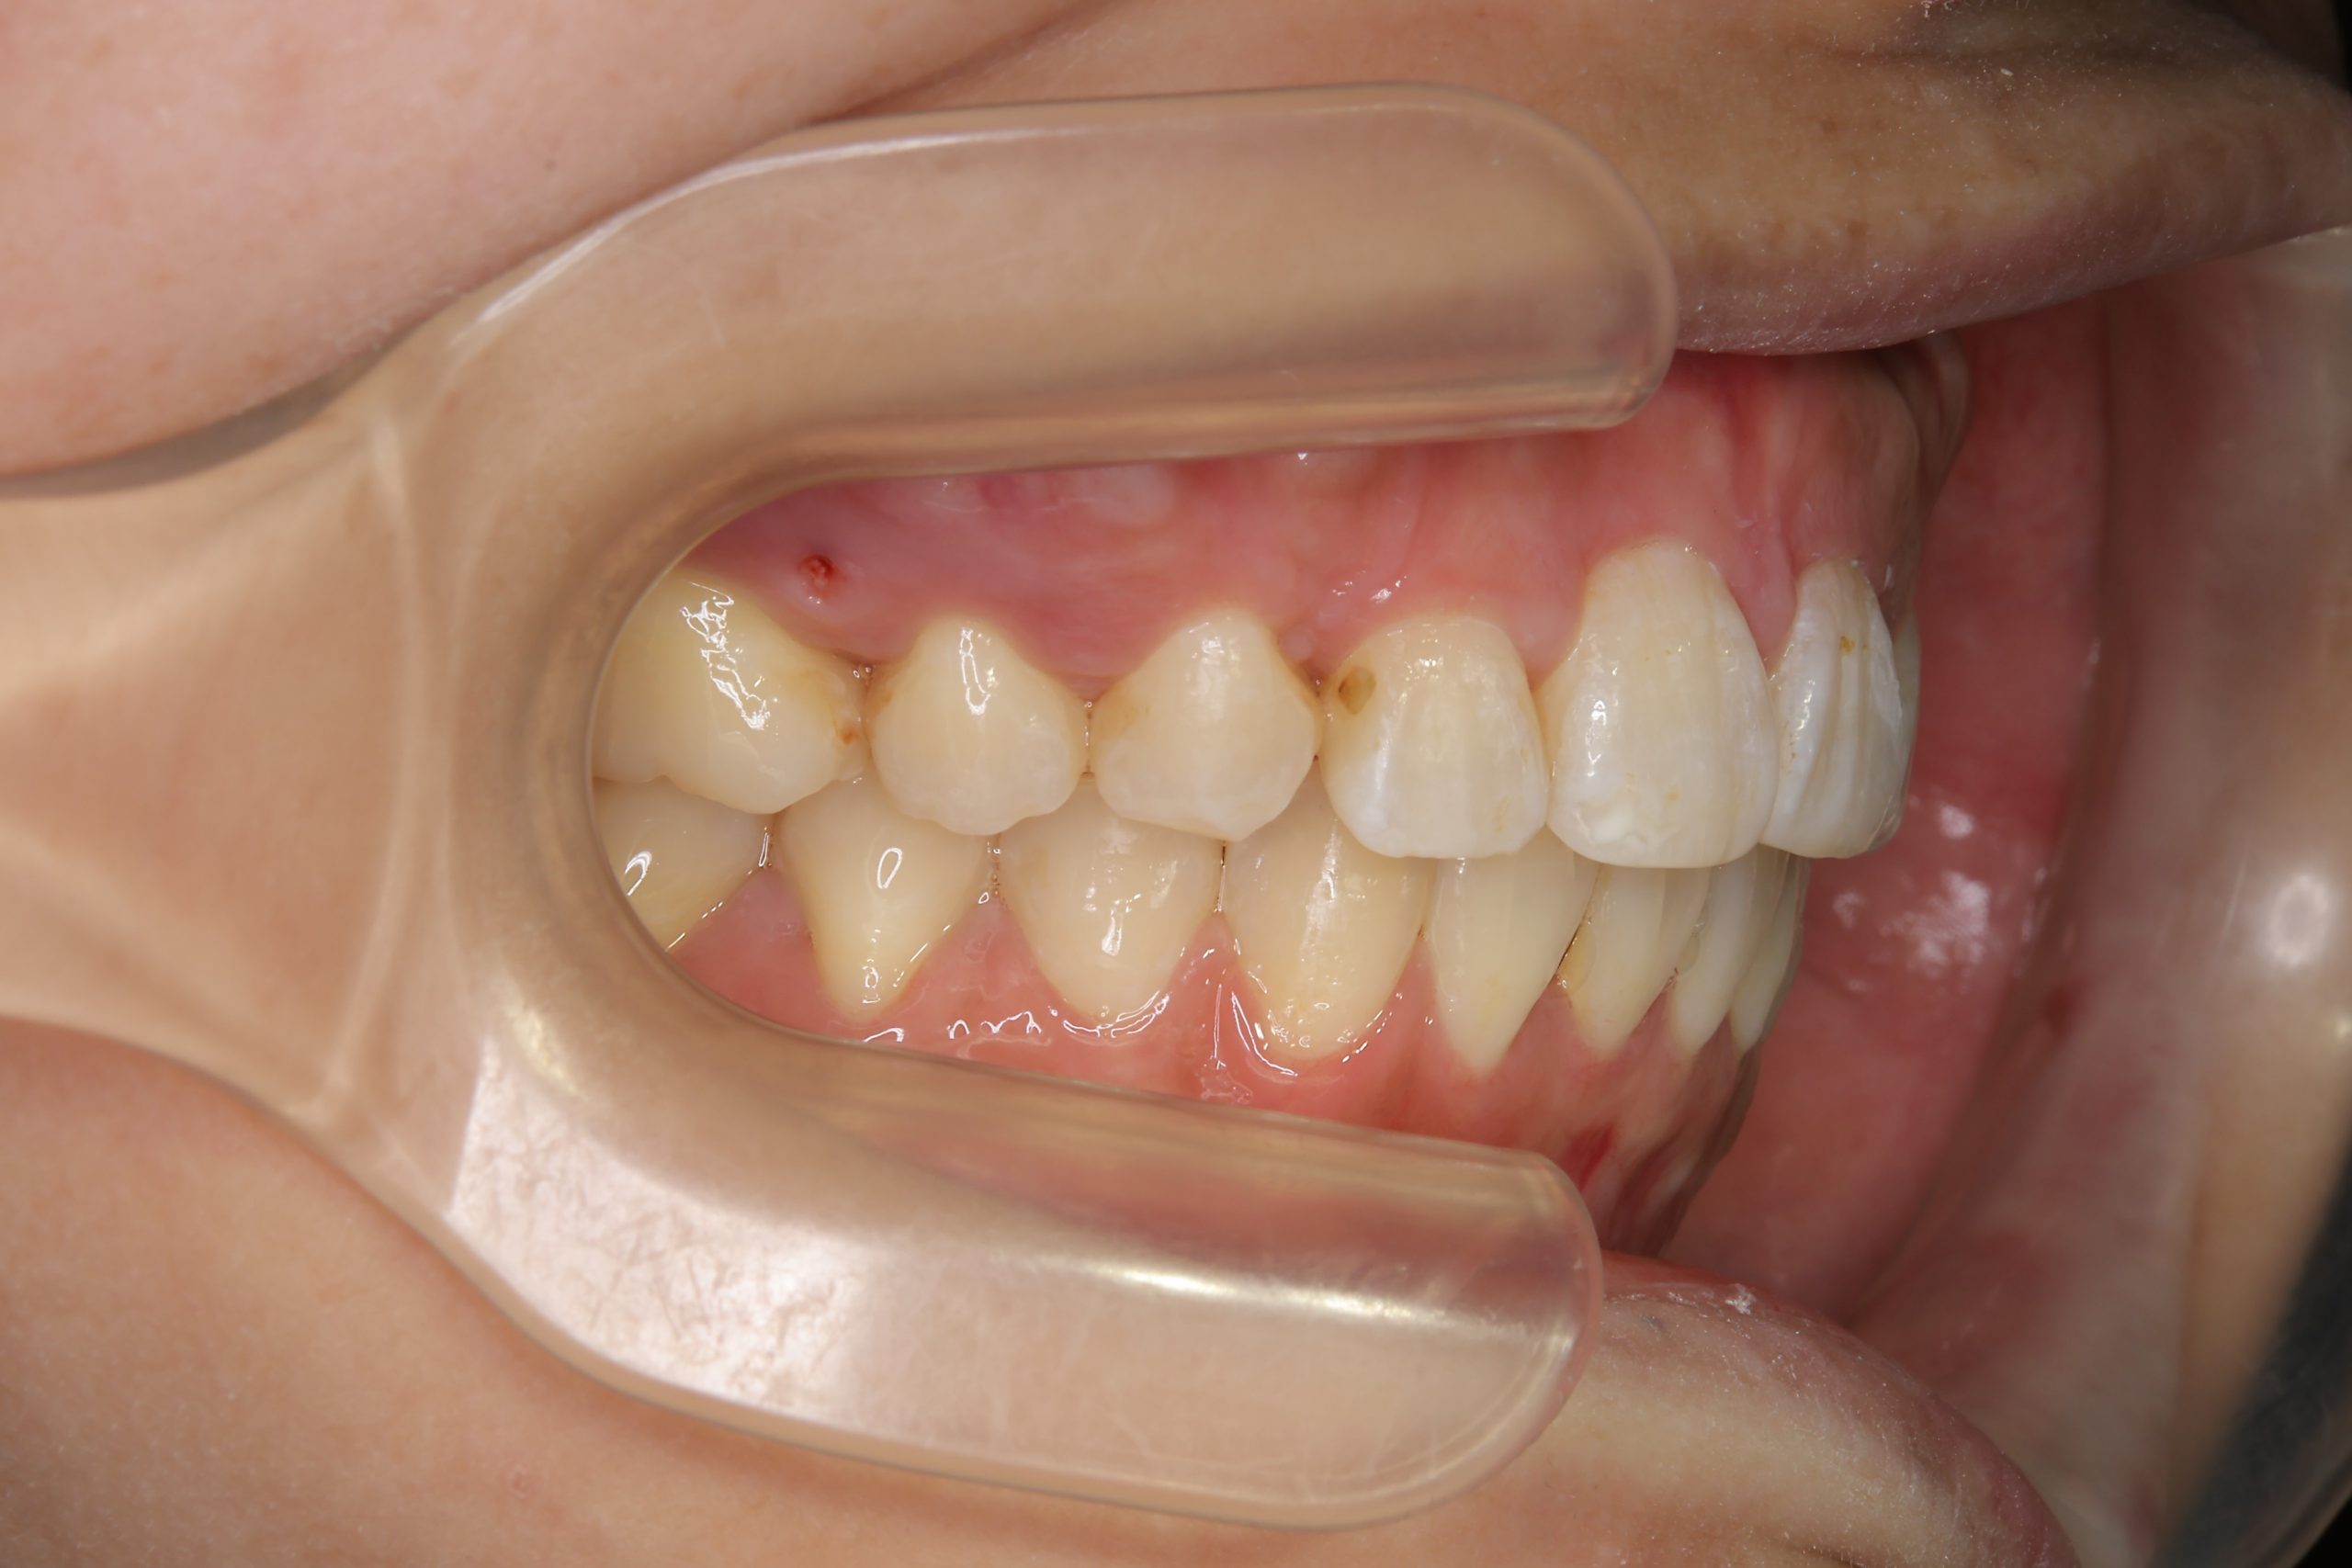

アフター

ワイヤー矯正治療|症例_814

施術内容 MSEと下顎リンガルアーチを用いて上下顎骨を拡大した。

その後上顎3・4番を抜歯しマルチブラケット装置とミニインプラントを用いて

歯牙を配列した。良好な咬合を獲得した。

治癒期間 1年8か月間